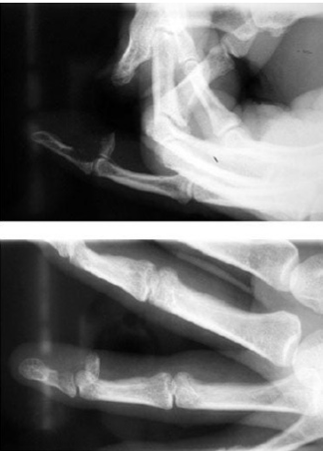

Name the splint

Ulnar gutter